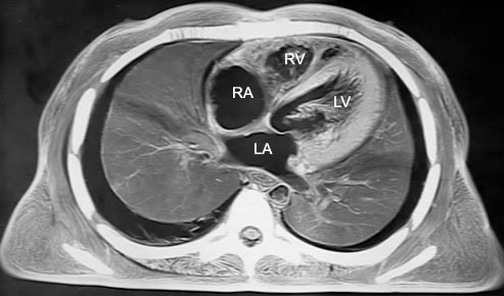

- The heart has four cavities:

- Right atrium

- Forms right margin of heart

- Left atrium

- Forms posterior margin of heart

- Right ventricle

- Forms anterior margin of heart

- Left ventricle

- Forms apex of heart